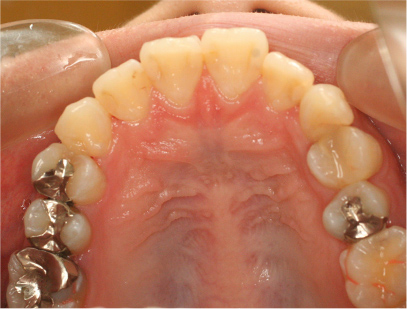

治療後

• 上側

治療前の写真と比べると上下の前歯は後方に下がりました。

そのために、鼻の下の膨らみもすっきりして、下唇も薄くなることができました。

治療期間は2年と6か月を必要としました。